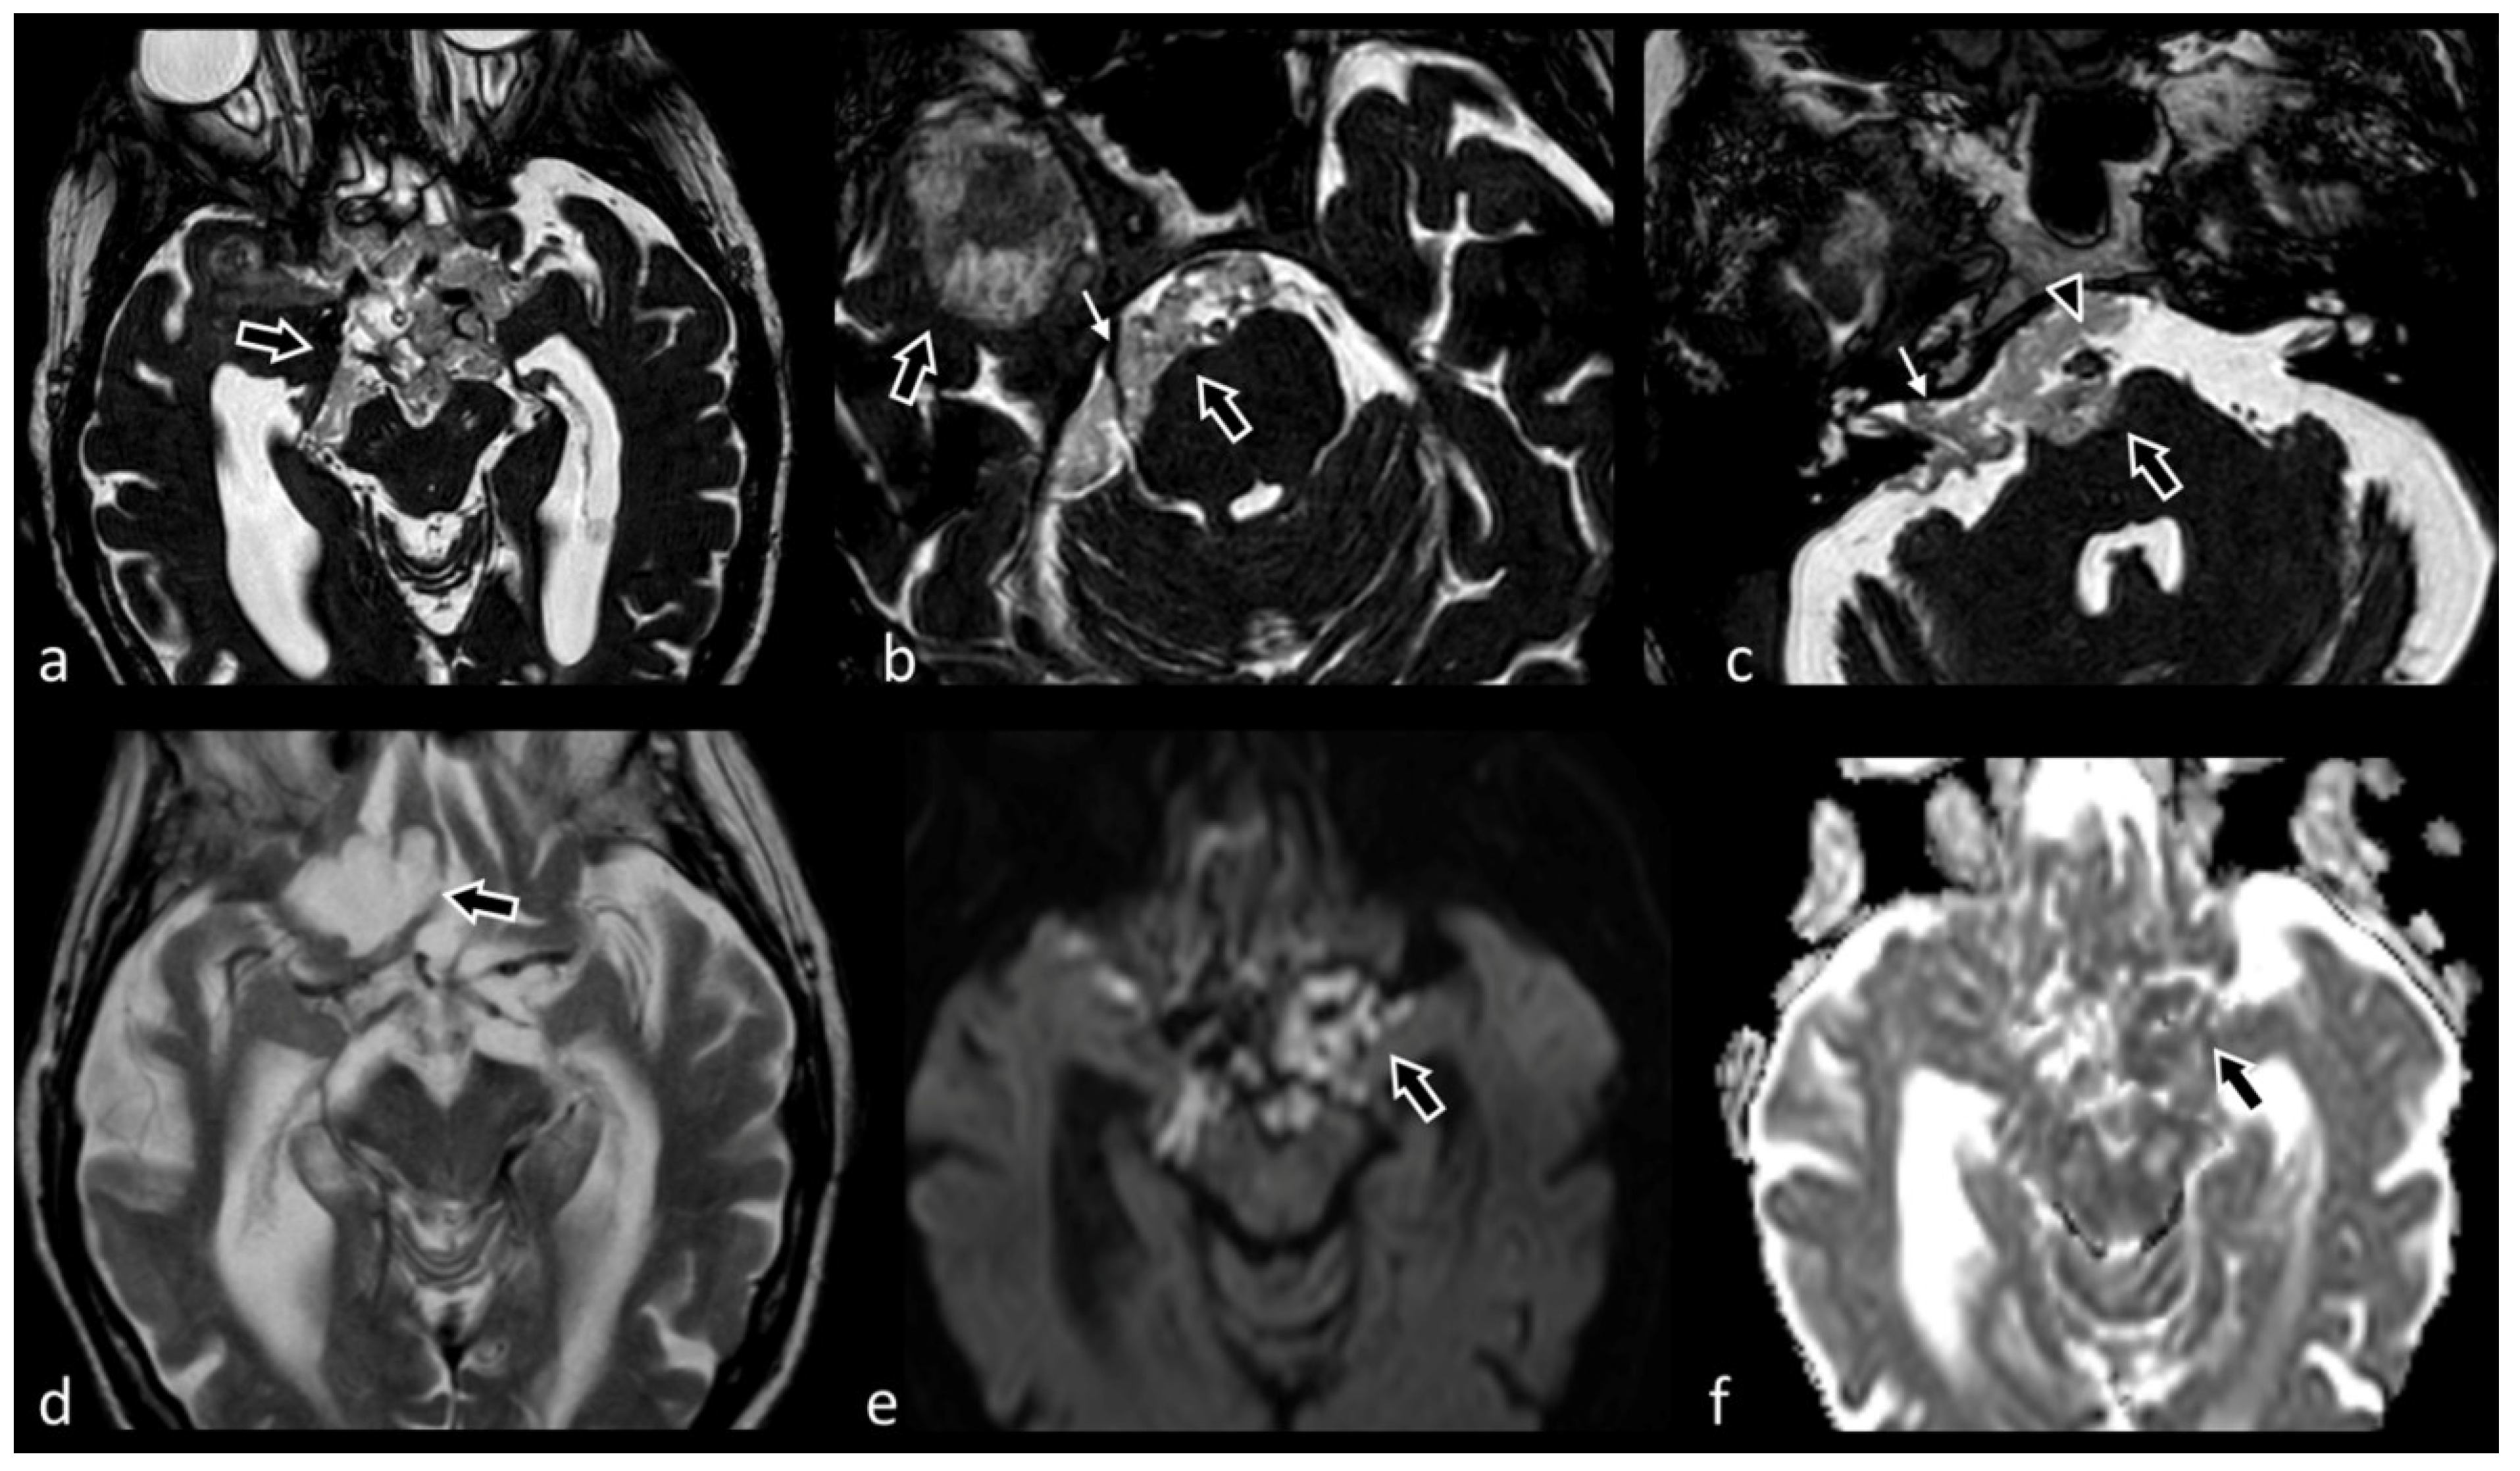

3.1.4. Trigeminal Nerve (V)

3.1.5. Facial and Vestibulocochlear Nerves (VII–VIII Complex)